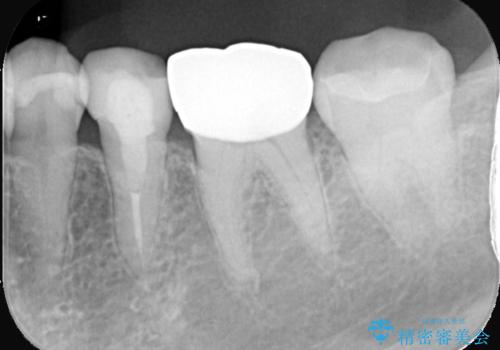

- 銀歯を白くしたいとのことでした。材料の違いを説明し、セラミックインレーでの治療となりました。

接着操作時にラバーダム防湿を行いました。

※左下6番は他のDrで治療を行っています。